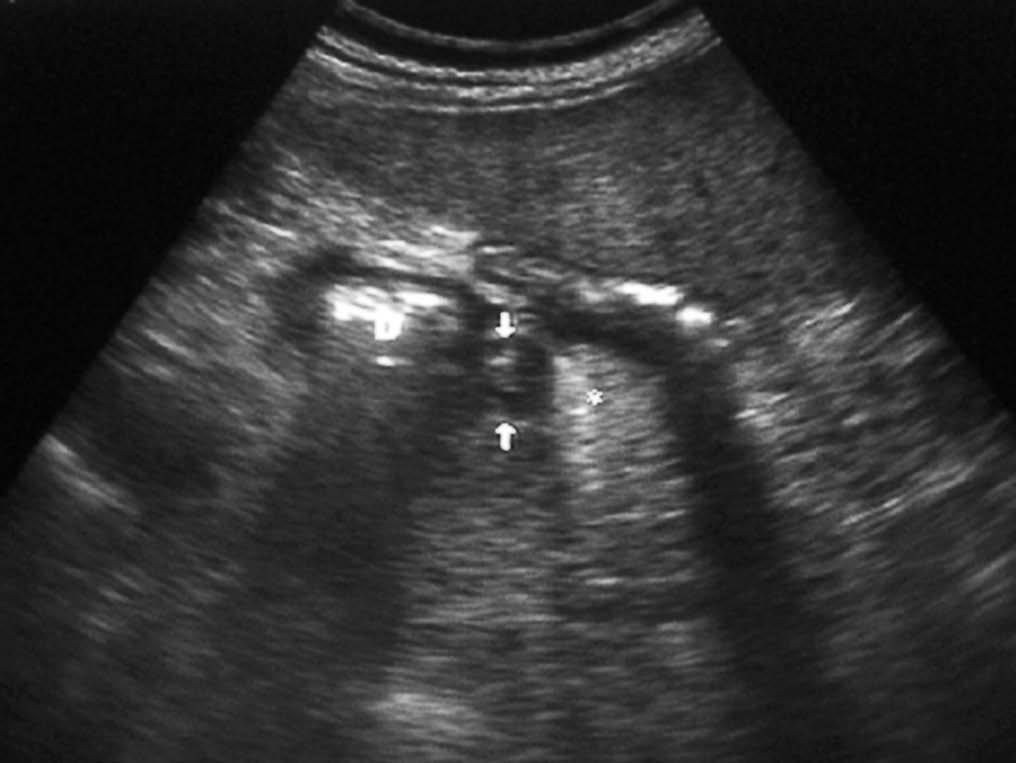

El duodeno es una localización infrecuente de diverticulitis. La imagen radiológica consiste en un engrosamiento de la pared del duodeno asociado a un divertículo, en ocasiones con un enterolito en su interior, con inflamación de la grasa adyacente16 (fig. 9).

Fig. 9--Diverticulitis duodenal. (A) En la ecografía se observa un divertículo (flechas) con engrosamiento de pared duodenal (D) y alteración de la grasa adyacente (*). (B) Tomografía computarizada de otro paciente con inflamación de divertículo duodenal. Se oberva una lesión quística (punta de flecha) de pared gruesa y borrosa, con material en su interior. P: Páncreas.